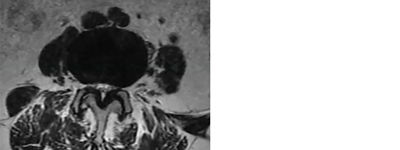

Identifying anatomical landmarks in a mild® patient

Photo Courtesy of James Lynch, PA – L3/L4 interspace

My specific area of interest in evaluating the mild® patient candidate is the small black area, which is the ligamentum flavum, highlighted in the image here.

In the small white area, we can see the central canal where the nerves are housed. In this image, we can see that the canal is very small, with very little white showing. This is consistent with central canal stenosis, and in this case, we can see clearly that the hypertrophic ligamentum flavum is compressing the nerves.